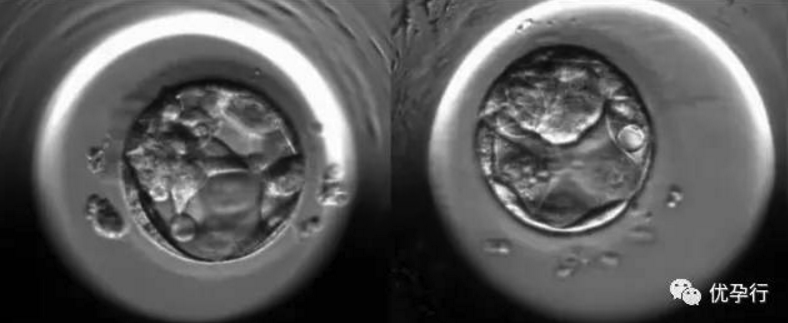

桑葚胚的細胞繼續分裂,細胞間逐漸出現小的腔隙,大約2天后它們較后匯合成一個大腔,桑葚胚轉變為中空的胚泡。胚泡也就是囊胚,這個時候是受精卵成活的第5天。早期胚胎發育到囊胚的這兩天是非常關鍵的,對溫度、空氣含氧量、二氧化碳含量的要求都非常高。